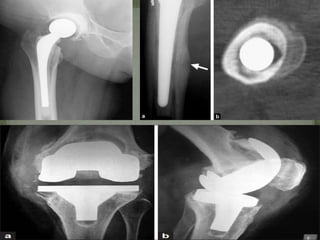

Prosthetic joint infections

• 1.

PRESENTED BY –Dr ANURAG RANA MODERATOR – Dr DEVENDRA CHOUHAN